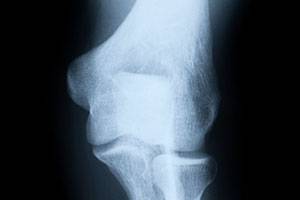

Первичные очаги чаще встречаются в проксимальном эпифизе большеберцовой кости (50%) и в дистальном эпифизе бедренной кости (21,7%), реже в метафизах этих костей (соответственно в 10% и 2,3% случаев), и совсем редко в надколеннике и эпифизе малоберцовой кости (2,2%). Первым рентгенологическим симптомом туберкулезного процесса является ограниченный участок остеопороза с нечетким рисунком костных трабекул. Затем появляется нечетко очерченный очаг деструкции костной ткани, который может содержать губчатые мелкие секвестры.

Очаги деструкции могут быть крупными, нередко в форме песочных часов, что характерно именно для поражения коленного сустава. При наиболее частой, эпиметафизарной локализации, очаги деструкции костной ткани обычно располагаются субкортикально. Периоститы не характерны.

Рентгенологические проявления туберкулезного гонита достаточно разнообразны. Однако самым ранним симптомом перехода туберкулезного процесса на сустав является нарастающий диффузный или пятнистый остеопороз, который постепенно распространяется на кости всей конечности. Причем, чем более остро протекает туберкулезный процесс, тем более выражен остеопороз.

У детей отмечается увеличение размеров эпифизов, по сравнению со здоровой конечностью, одновременно может увеличиваться ядро окостенения надколенника (симптом «постарения эпифизов» С. Л. Трегубова).

Постепенно нарастает сужение суставной щели, которое иногда может быть неравномерным, больше выраженным с одной стороны. Однако этот признак иногда может быть кажущимся, и связан с небольшой сгибательной контрактурой. В таких случаях необходимо производить для сравнения рентгенографию и здорового коленного сустава в том же положении.

Одновременно с сужением суставной щели появляется неровность, волнистость суставных поверхностей, затем появляется нечеткость, зазубренность, прерывистость контуров суставных поверхностей. Выявляются краевые очаги деструкции костной ткани, которые могут располагаться в противоположных отделах сочленяющихся костей и содержать секвестры, часто множественные.

Секвестры кажутся более плотными, «склерозированными» на фоне выраженного остеопороза, структура их губчатая, «ноздреватая», контуры неровные. Постепенно появляются признаки истинной атрофии костей.